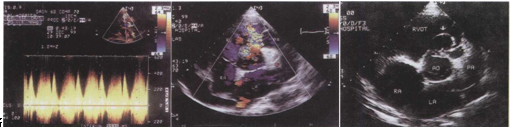

14.该病例最可能的诊断 ()